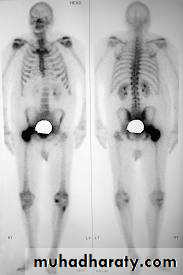

Metastasis of Prostate cancer

Local spread : seminal vesicles, B neck, trigone, distal sphincterLymph spread : Obturator, Int iliac, ext iliac / Mediastinal / Supraclavicular

Blood spread : Bones, liver , lungsClinical features

X-Ray of bones + Isotope Bone scan